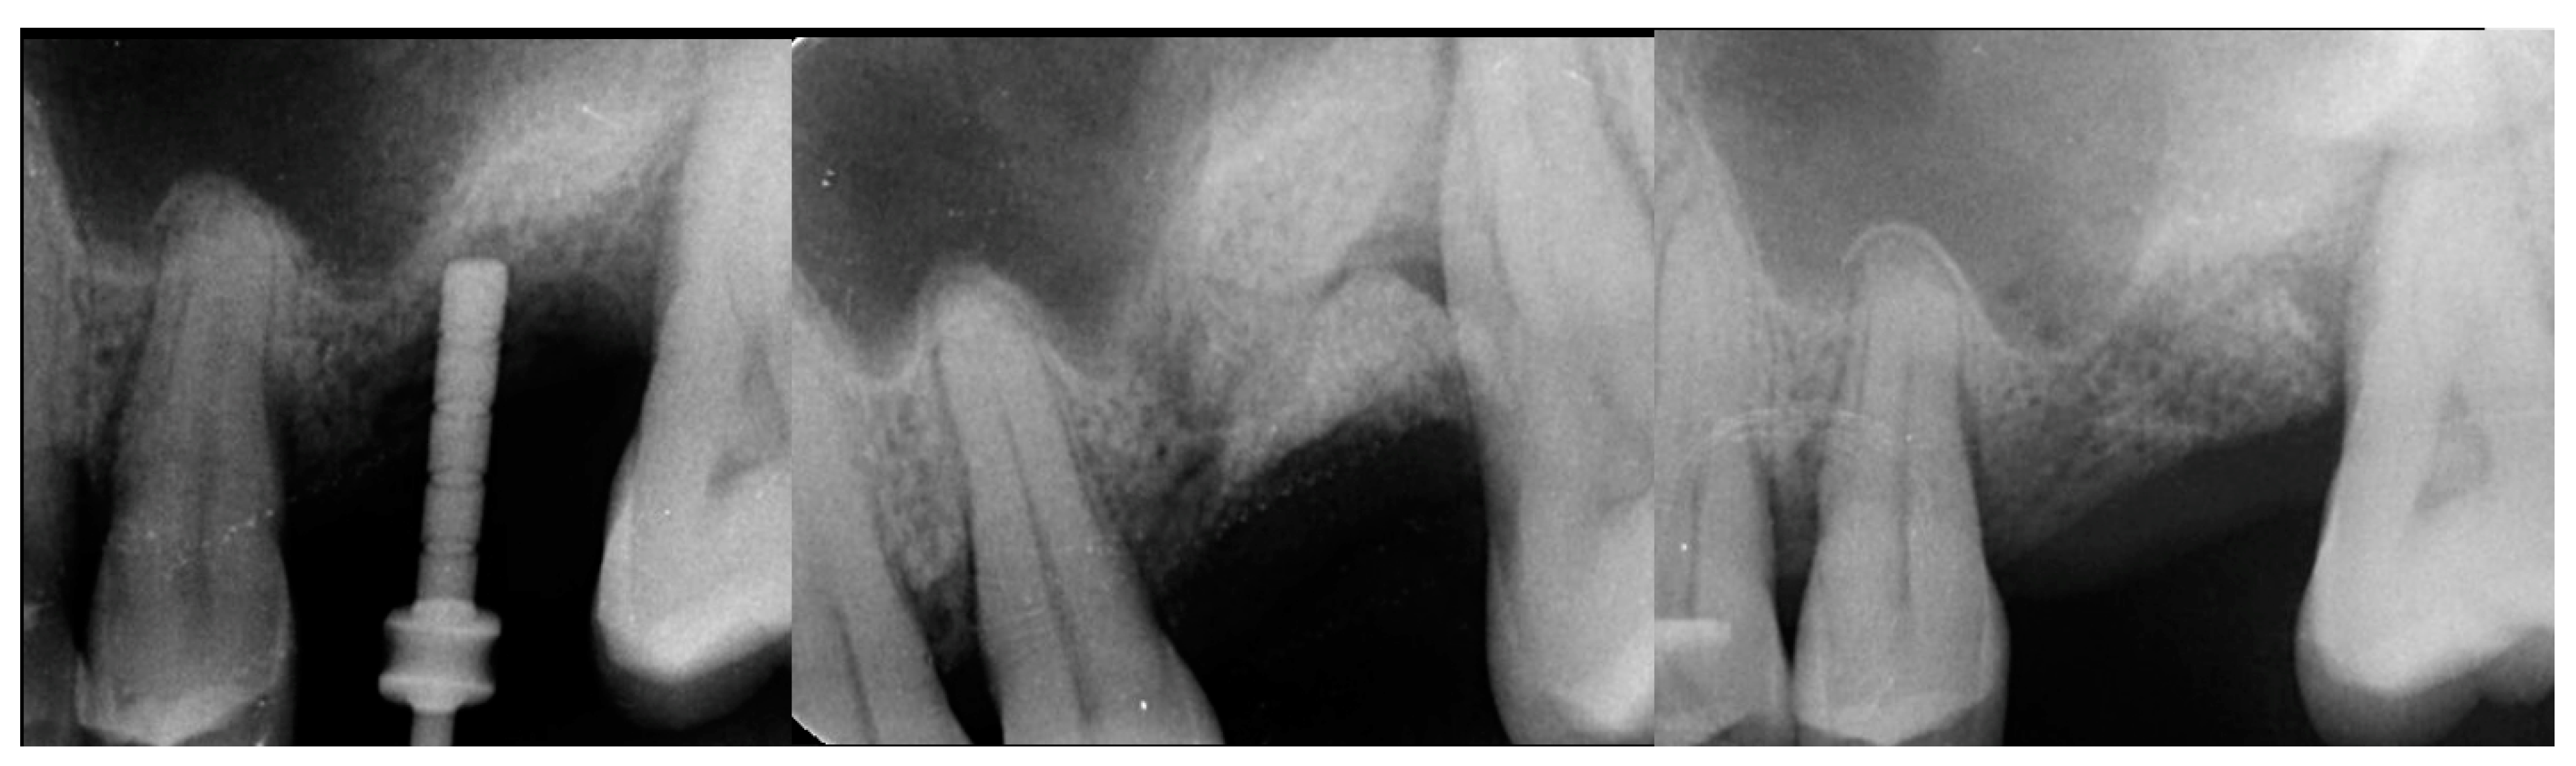

The patient returned at 10-weeks implant and graft placement and the soft tissue over the posterior quadrant was noted to be healed with no inflammation present (Figure 10 left). Following local anesthetic administration a full thickness flap was elevated and the previously grafted 2nd molar crestal area was filled with immature host bone (Figure 10 right). A radiograph was obtained, which noted a crestal height of 7.1 mm present (Figure 11 left). The 2nd molar site was prepared in a similar fashion as previously detailed, utilizing Densah burs to osseodensify the area and accomplish a crestal sinus augmentation and a 5 × 8.5 mm Anyridge implant was placed (Figure 11 middle and right). An impression of the 1st molar implant was obtained to initiate its restoration while the 2nd molar implant was integrating. A healing abutment was placed on the implant at the 1st molar and a cover screw on the 2nd molar implant and a radiograph obtained to document the clinical result to date (Figure 12).

Figure 11.

Radiograph demonstrating sufficient height of the ridge to allow primary stability of an implant placed at the 2nd molar with a crestal sinus augmentation at 10 weeks of graft healing (left), site preparation for the crestal sinus augmentation (middle) and implant placement into the site (right). Green line is the measurement of the height of the bone at that point between the crest and the sinus floor.

Figure 12.

Radiograph following implant placement into the 2nd molar site with simultaneous crestal sinus augmentation.

The patient returned at 10 weeks post-2nd-implant placement and a screw-retained restoration was placed on the 1st molar and a radiograph was obtained (Figure 13, left). Impressions were obtained and the restoration on the 2nd molar was placed at a subsequent appointment. Soft tissue was healthy at placement of the restoration on the 2nd molar and no marginal inflammation was noted at either site (Figure 14, left). Soft tissue at the 1-year recall remained healthy and lacking in inflammation (Figure 14, middle). At a 2-year recall, a radiograph was obtained and bone was noted to be stable at both implants (Figure 13, right). Soft tissue at the 2-year recall remained stable and no change in marginal position was noted compared to initial restoration placement (Figure 14, right).

Figure 13.

Radiograph at 10 weeks implant integration at the 2nd molar (left) and two years following restoration of the implant at the 2nd molar showing the improved vertical regeneration between the implants (right).